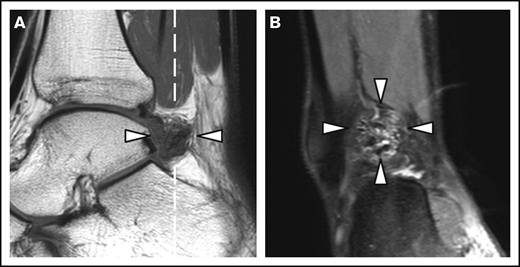

Patient and joint characteristics are presented in Table 1. At baseline, patients were aged 12 to 29 years. Prophylaxis was given in 15 (94%) of 16 patients with severe hemophilia (weekly dose, 38 IU/kg; IQR, 23-44 IU/kg) and in 1 (13%) of 8 patients with moderate hemophilia. Details on treatment and adherence have been published previously.11 Treatment remained unchanged during follow-up. None of the patients was treated for clinical synovitis at baseline. Clinical function was good according to the Hemophilia Joint Health Score (HJHS) assessed within 2 years of MRI (median HJHS, 0; IQR, 0-1). The majority of joints (82%) had a history of bleeding before MRI (median lifetime number of joint bleeds/joint, 2; IQR, 1-5). At baseline, the AJBRs for knees and ankles combined were low (median, 0.2; IQR, 0.5-1.2). Although radiographic abnormalities were observed in 7% of joints only, 39% of joints showed MRI abnormalities, including 24 of 48 ankles and 15 of 52 knees. The most prevalent MRI findings were effusion (23%), synovial hypertrophy (16%), and hemosiderin deposits (16%). Synovial hypertrophy and hemosiderin deposits were mostly concurrent findings; 14 of 16 joints (87.5%; confidence interval [CI], 61.7-98.5) with synovial hypertrophy showed hemosiderin deposits, and 14 of 16 joints (87.5%; CI, 61.7-98.5) with hemosiderin deposits showed synovial hypertrophy. Ankles exhibited synovial hypertrophy and hemosiderin deposits significantly more often than knees (P < .01). Figure 1 presents an example of concomitant findings of synovial hypertrophy and hemosiderin deposits in an ankle. There were no significant differences in the baseline joint characteristics between patients with moderate hemophilia treated on demand and patients with severe hemophilia on prophylaxis, nor in bleeding rates during follow-up.

MRI of a right ankle with synovial hypertrophy and hemosiderin deposits. Synovial hypertrophy and hemosiderin deposits (arrowheads) on a sagittal T1-weighted MRI (A) and the coronal proton density–weighted MRI with fat suppression (B). The dashed white line in panel A represents the imaging plane of panel B.